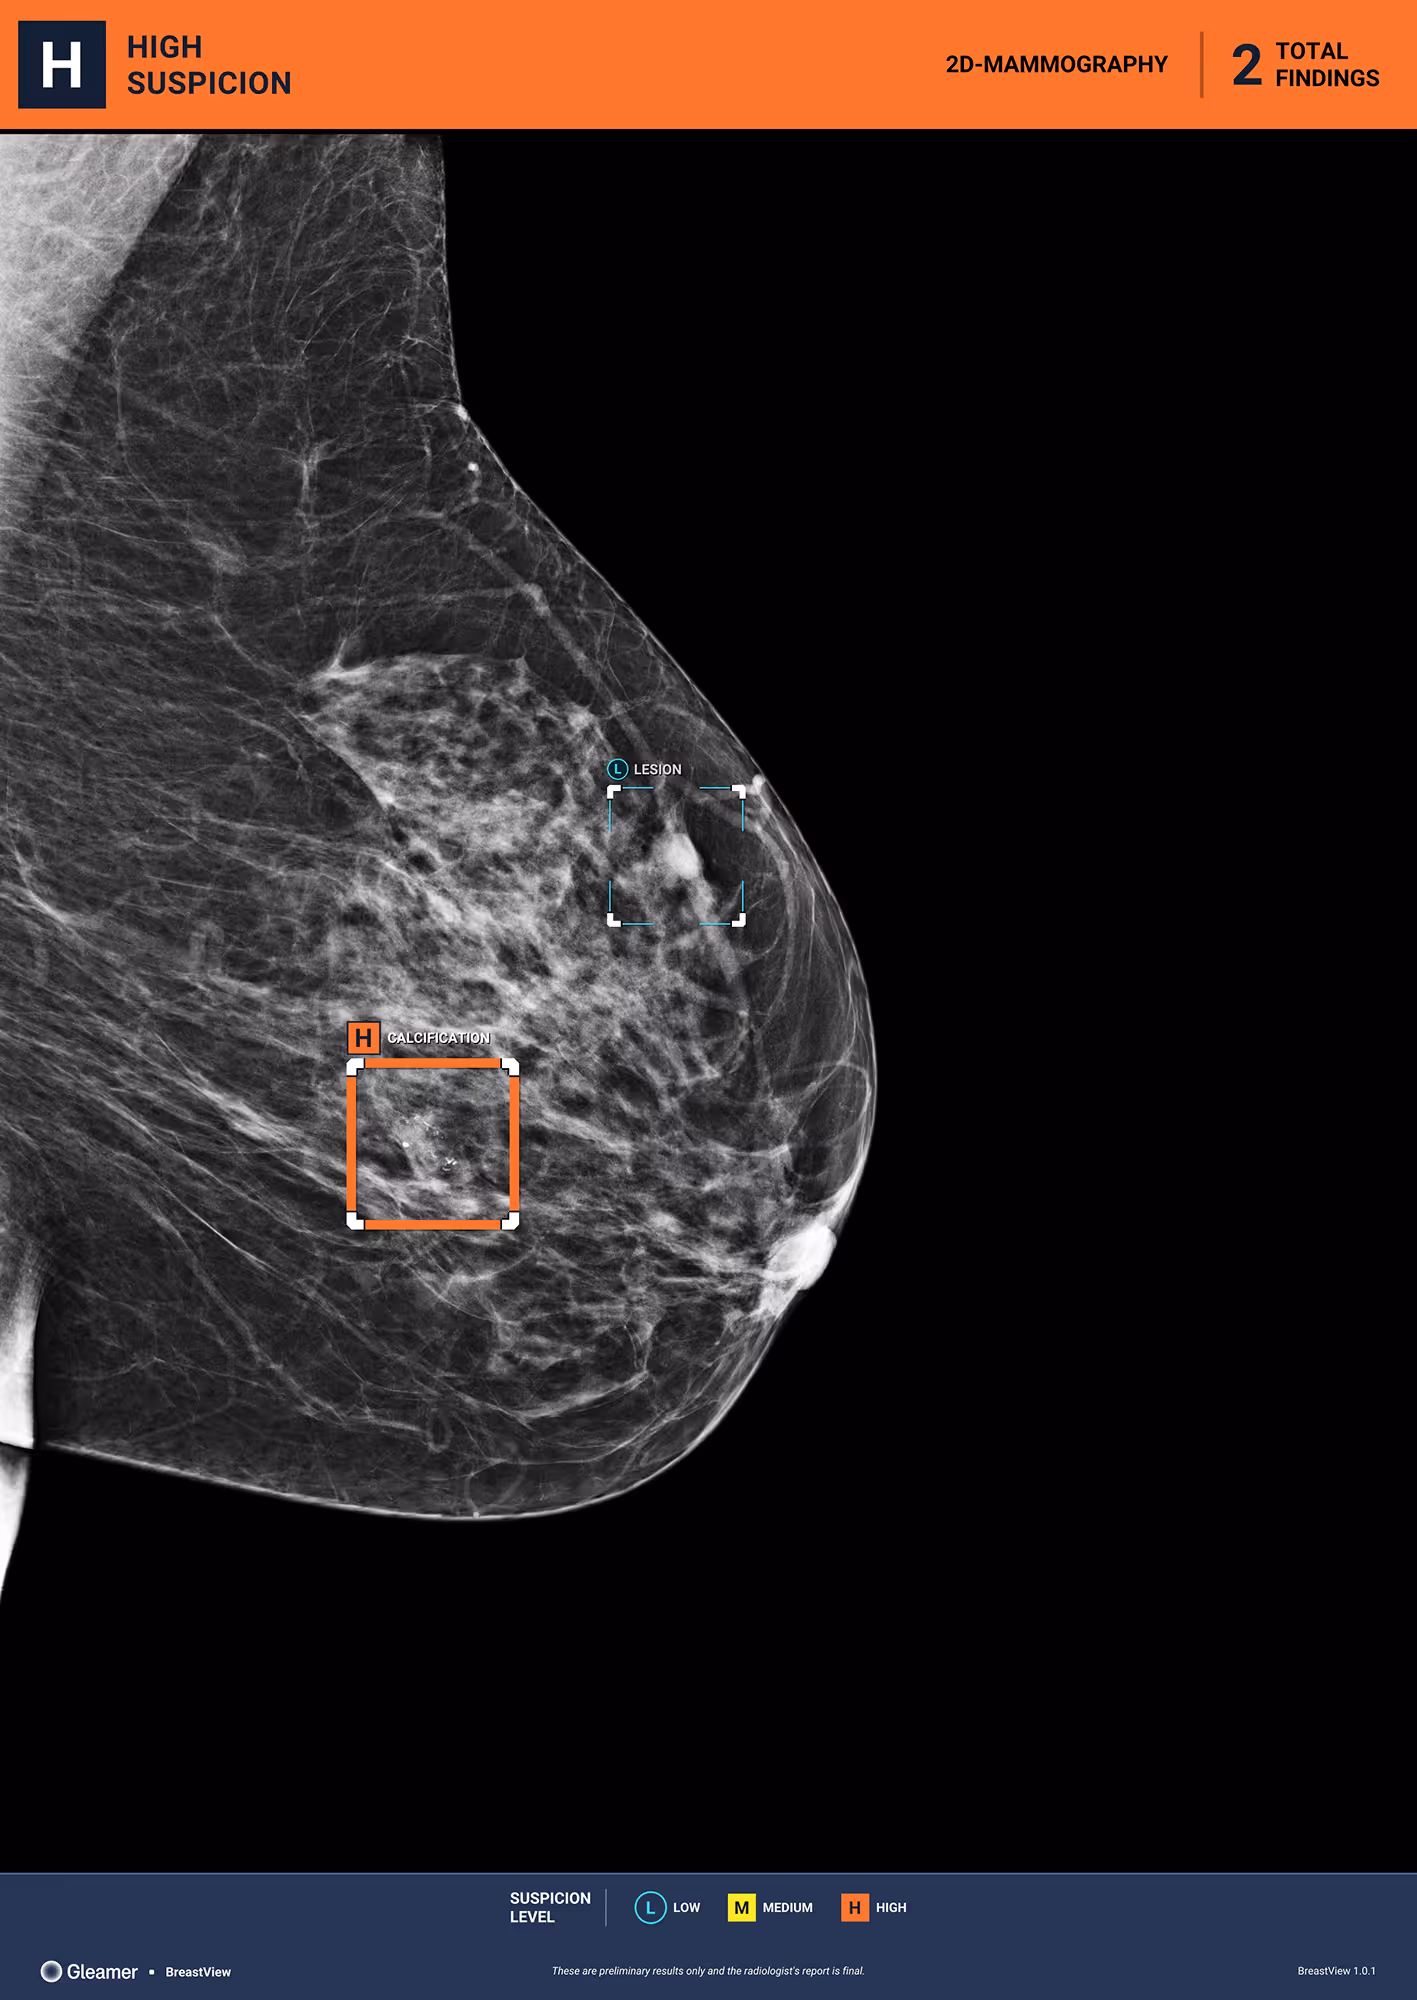

56 y.o patient presenting as part of organized screening.

Results

BreastView detected a benign cyst and micro-calcifications that were a ductal carcinoma in situ (DCIS).